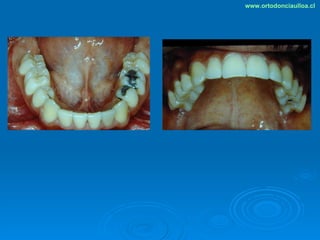

Este documento presenta dos casos clínicos de pacientes que recibieron tratamiento de ortodoncia. El primer caso fue de una paciente femenina de 14 años con apiñamiento dental y mordida cruzada que fue tratada mediante extracción de premolares y alineamiento dental. El segundo caso fue de un paciente masculino de 14 años con clase II esqueletal y desarmonía dentomaxilar que fue tratado con extracción de premolares y corrección de mordida. Ambos casos mostraron mejoría después de 3 años de tratamiento.